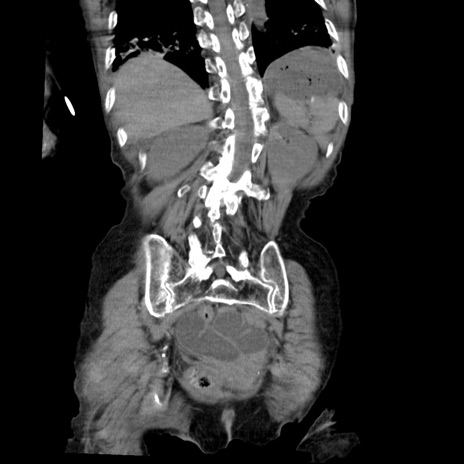

症例27(冠状断像)

【症例】80歳代女性

【主訴】嘔吐、腹痛

【現病歴】数時間前より嘔吐あり。心窩部痛出現し、徐々に右下腹痛あり。その後も数回嘔吐あり救急搬送となる。

【既往歴】左大腿骨頚部骨折手術

【身体所見】腹部は膨隆しているが軟らかく圧痛なし。腸雑音はやや亢進。

【データ】WBC 12000、CRP 19.05